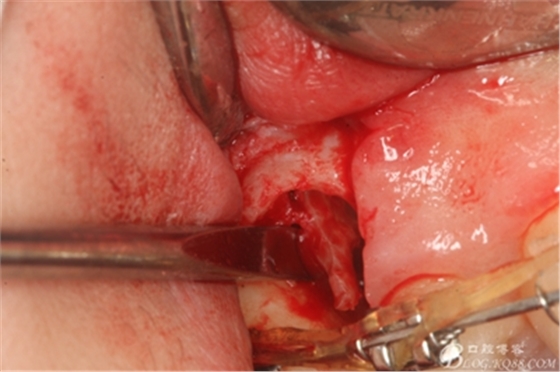

圖14.用小球鉆縱分15牙根

圖15 .微創(chuàng)挺把15牙根縱分成近遠(yuǎn)中兩塊

圖16.微創(chuàng)挺挺松近中根面部分,從16與14之間間隙出來